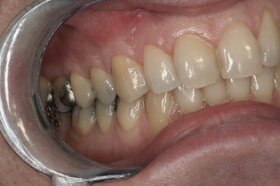

A fogágybetegség kezelése után a beteg fogszabályozó készüléket kap az esztétikai eltérés korrekciójára

A kezelés végén a fogszabályozó készülék eltávolítása előtt

A végeredmény, a frontfogak a belső oldalon összesínezve